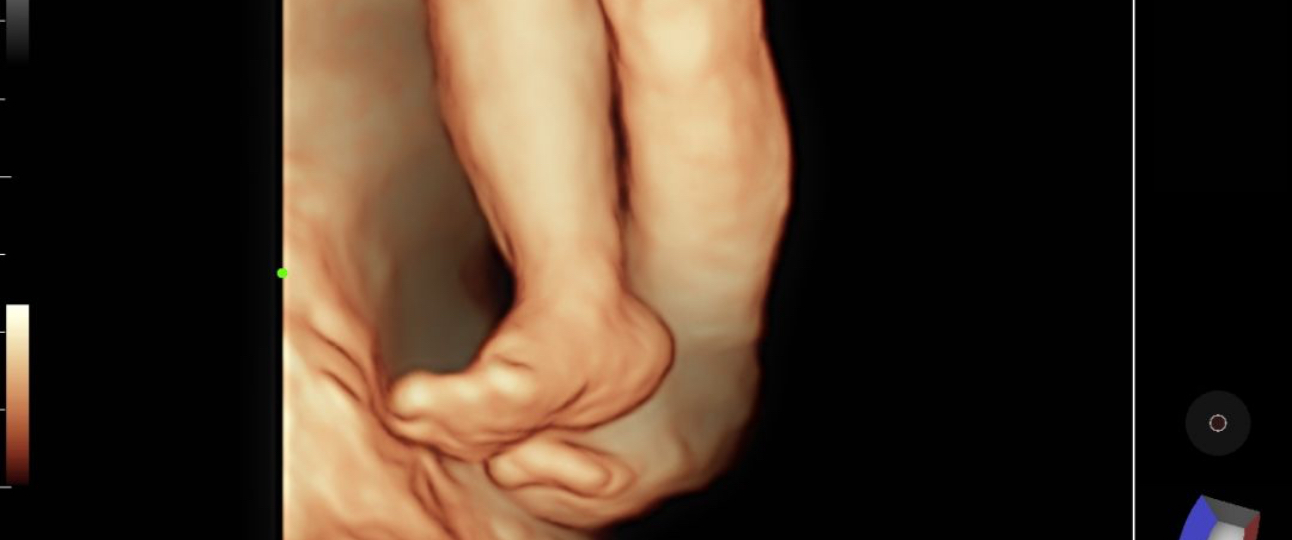

The popularity of the device is largely attributed to its performance in OB-GYN. It excels not only in the breadth of 3D/4D projection imaging, but also in the precision of various details in GYN. In these two major fields, it does a wonderful job with ease, demonstrating eXpress Clarity with remarkable accuracy.

3D/4D performance